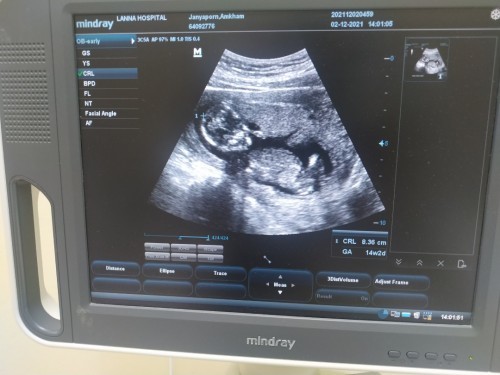

ตอนนี้น้องได้ 18+5 แล้วค่ะ